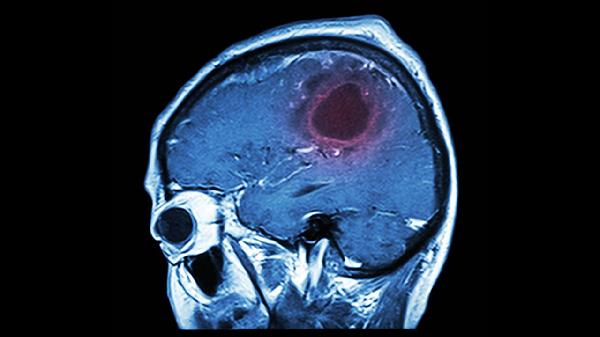

2、头部磁共振成像

头部磁共振成像对脑组织分辨率高,可早期发现缺血性脑梗死。弥散加权成像能在发病数分钟内显示缺血病灶,灌注加权成像可评估脑血流灌注情况。磁共振血管成像无需造影剂即可显示脑血管形态,但检查时间长,体内有金属植入物者禁用,幽闭恐惧症患者可能难以耐受。